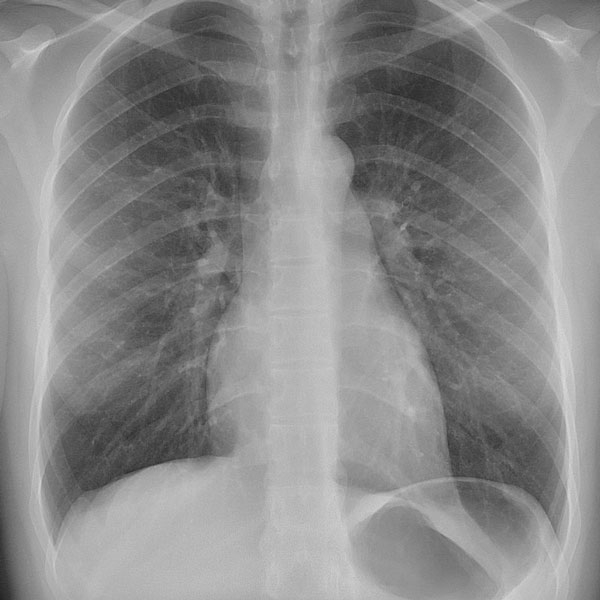

Conceitos básicos, Diagnóstico, Órgãos afetados, Comprometimento Pulmonar, Tratamento Multidisciplinar, Fisioterapia, importância da Fisioterapia na Fibrose Cística, Abordagem fisioterapeutica para criança, adolescente e adulto, Novas diretrizes e tomadas de decisão.